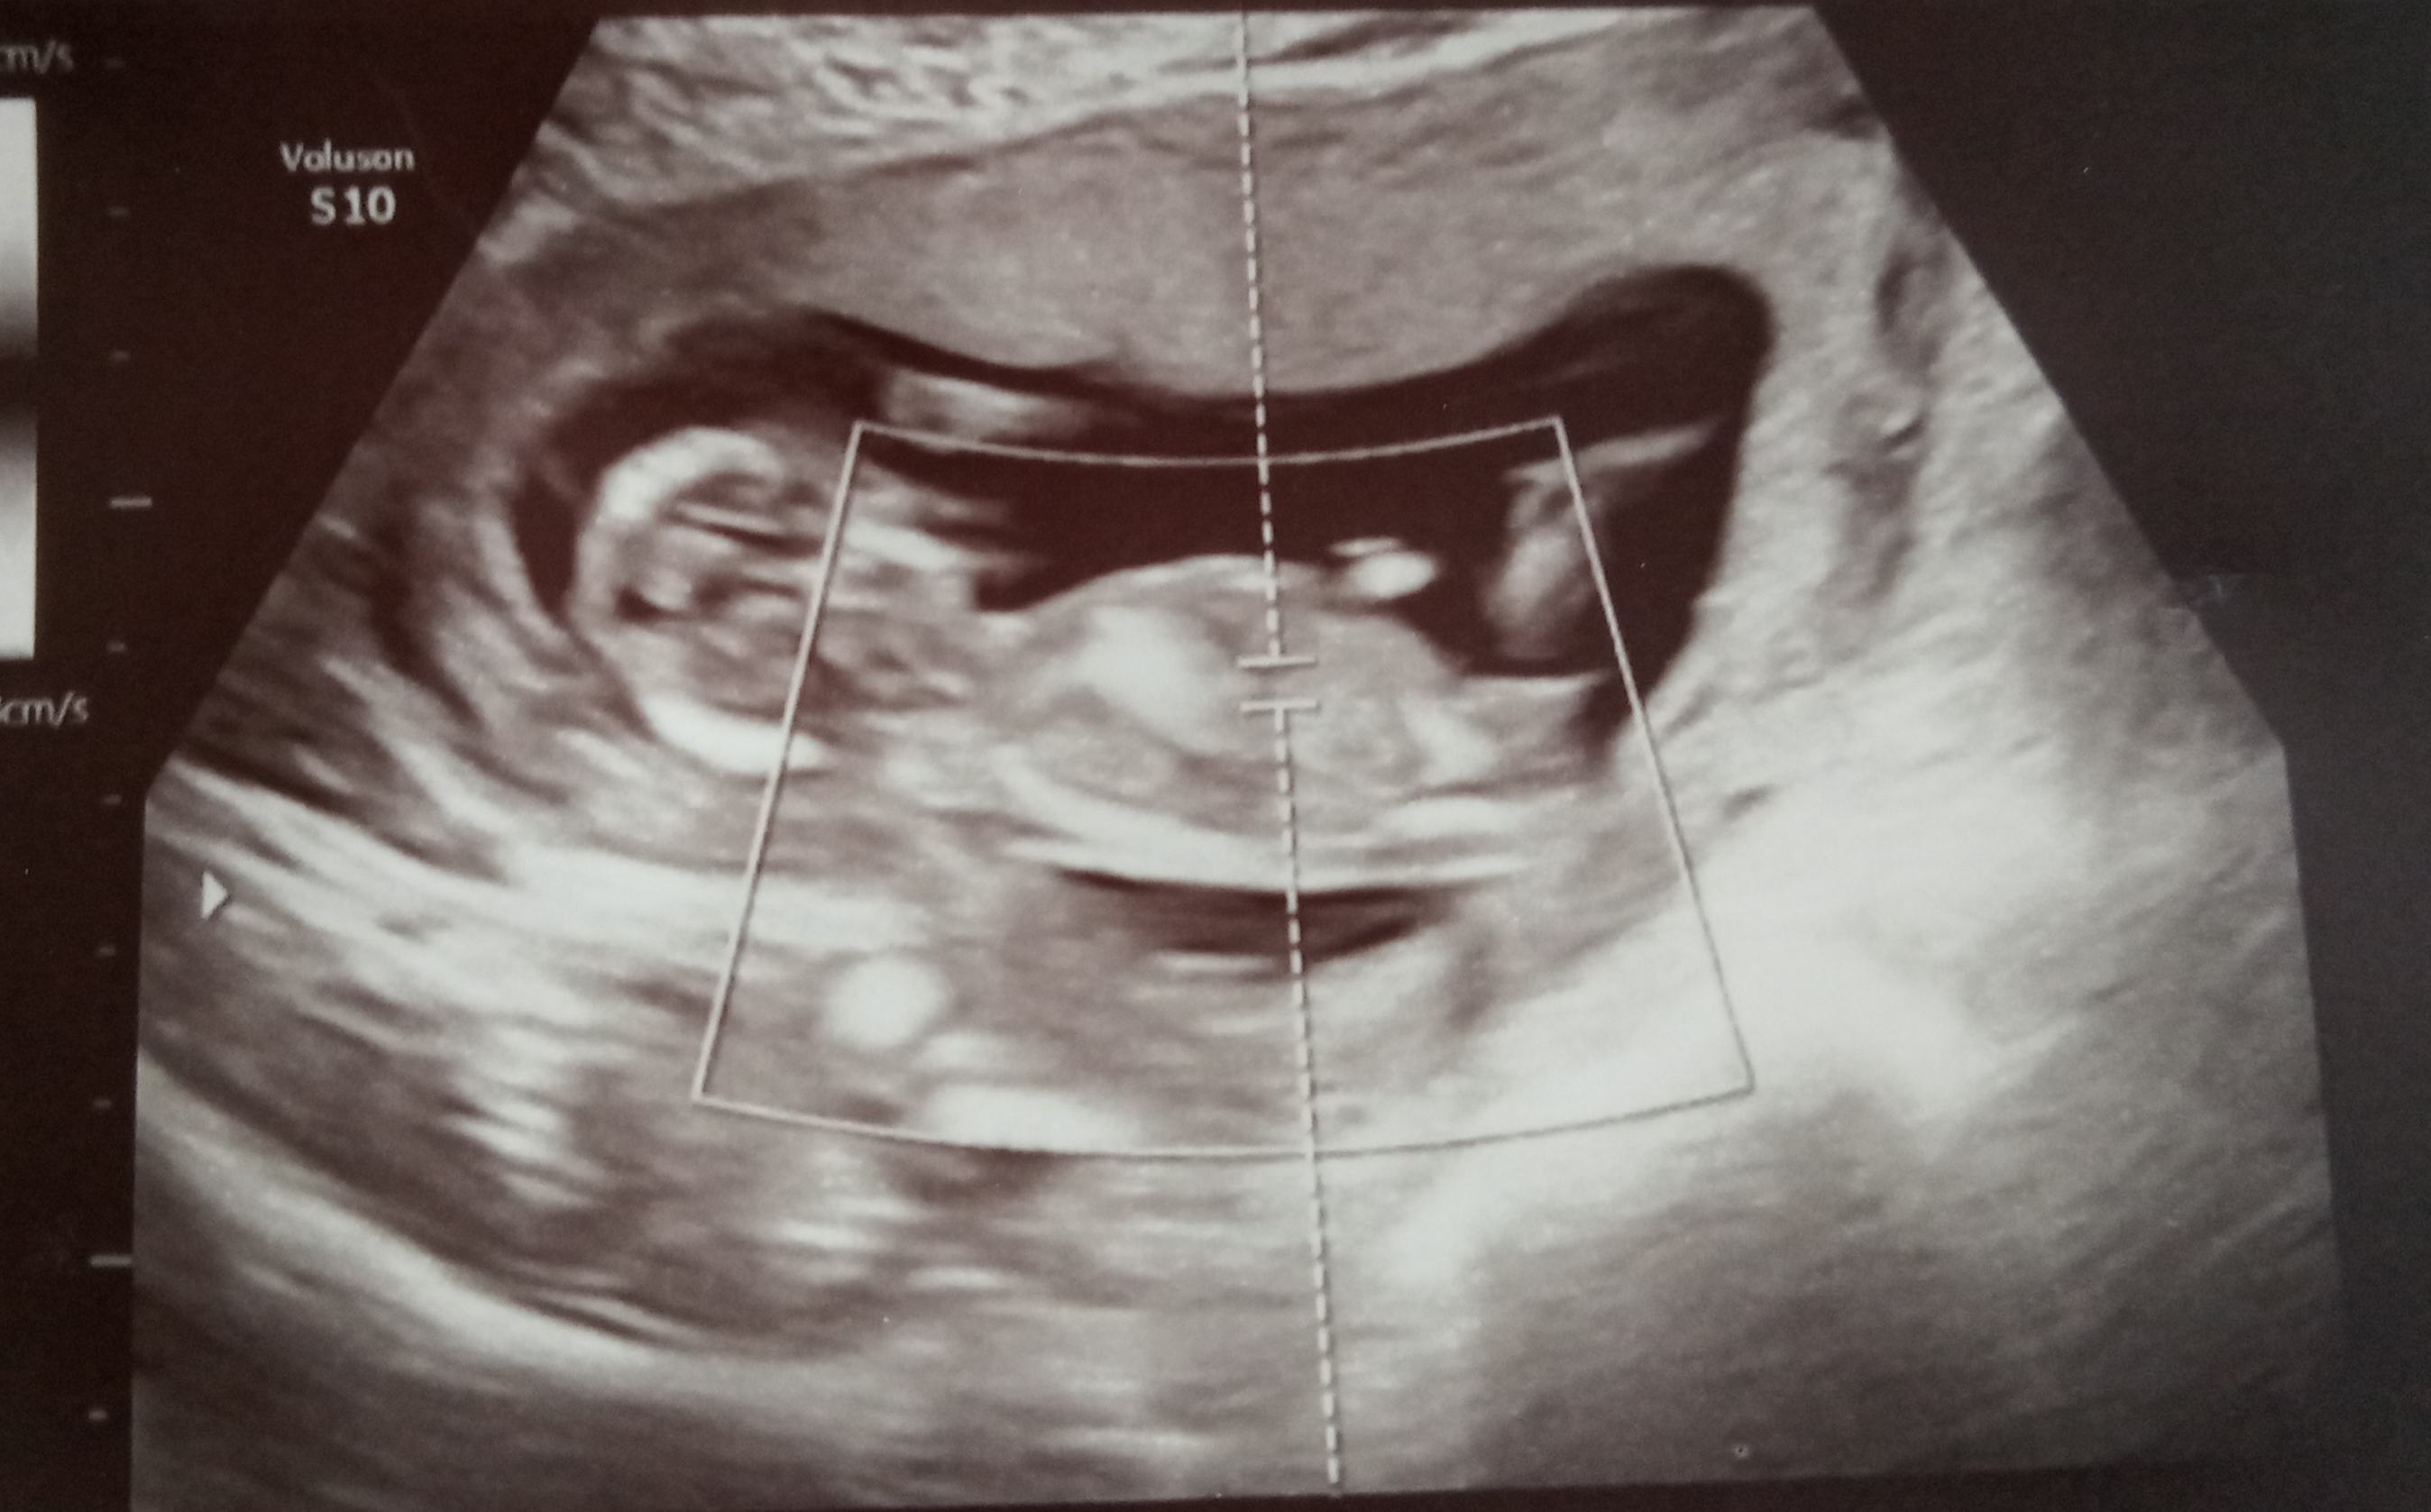

Guess 13w3d NT scan, what do you guys think?

I have no idea if itīs possible to tell by looking at these pics. Boy or girl, what do you think?

Maybe girl.

Tentative pink lean but I think the baby may have been in motion.